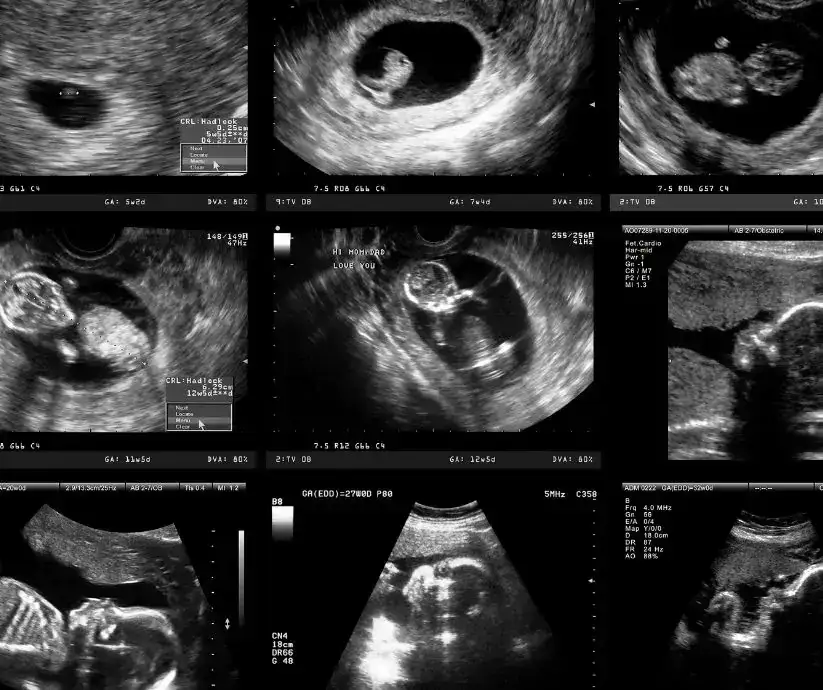

Kiedy widać ciążę na usg? To pytanie nurtuje wiele przyszłych mam, które pragną jak najszybciej potwierdzić swoją ciążę i zrozumieć, co dzieje się w ich ciele. Badanie ultrasonograficzne (USG) jest kluczowym narzędziem w diagnostyce ciążowej, które pozwala na wczesne wykrycie ciąży i monitorowanie jej przebiegu. Już w 4. tygodniu ciąży można zobaczyć pierwsze oznaki, takie jak pęcherzyk ciążowy, co potwierdza, że ciąża rozwija się wewnątrzmacicznie.

W kolejnych tygodniach, takich jak 5. i 6., na USG można dostrzec pęcherzyk żółtkowy oraz zarodek, a także jego czynność serca. Warto znać te kluczowe momenty, aby móc lepiej zrozumieć rozwój ciąży oraz odpowiednio się do niej przygotować. W tym artykule przyjrzymy się, kiedy i co dokładnie można zobaczyć na badaniach USG wczesnej ciąży.

Wczesne etapy ciąży są niezwykle ważne dla każdej przyszłej mamy. Ciążę można zobaczyć na badaniu USG już w 4. tygodniu ciąży, licząc od pierwszego dnia ostatniej miesiączki. W tym czasie na ultrasonografie pojawia się pęcherzyk ciążowy, co potwierdza, że ciąża rozwija się wewnątrzmacicznie. To kluczowy moment, ponieważ pozwala wykluczyć ciążę pozamaciczną, która może stanowić zagrożenie dla zdrowia.

W 5. tygodniu ciąży na USG można dostrzec pęcherzyk żółtkowy, który znajduje się wewnątrz pęcherzyka ciążowego. To ważny znak, że ciąża rozwija się prawidłowo. W tym okresie może również pojawić się pierwsze echo zarodka, co jest kolejnym krokiem w monitorowaniu rozwoju ciąży. Najczęściej zarodek staje się widoczny na USG dopochwowym około 6. tygodnia ciąży, a czynność serca płodu można zaobserwować już między 5. tygodniem +5 dniem a 6. tygodniem +1 dniem ciąży.

Jakie elementy ciąży są widoczne na usg wczesnym?

Wczesne badanie USG pozwala na obserwację kilku kluczowych elementów ciąży. W miarę postępu ciąży, na USG można dostrzec pęcherzyk żółtkowy oraz, w późniejszych tygodniach, zarodek. Pęcherzyk żółtkowy jest pierwszym źródłem składników odżywczych dla rozwijającego się płodu, zanim łożysko przejmie tę funkcję. Jego obecność jest oznaką zdrowego rozwoju ciąży i może być widoczny już w 5. tygodniu.

W miarę jak ciąża się rozwija, w 6. tygodniu można również zauważyć zarodek oraz jego czynność serca. To moment, w którym przyszłe mamy mogą poczuć radość i ulgę, gdyż widok bijącego serca jest silnym symbolem zdrowia i życia. Wczesne USG jest więc nie tylko narzędziem diagnostycznym, ale także emocjonalnym wsparciem dla przyszłych rodziców, którzy pragną upewnić się, że ich dziecko rozwija się prawidłowo.

Zarodek i czynność serca: Kiedy stają się widoczne?

W miarę postępu ciąży, w 6. tygodniu na badaniu USG można zauważyć zarodek oraz jego czynność serca. To moment, w którym przyszłe mamy mogą poczuć radość i ulgę, ponieważ widok bijącego serca jest silnym symbolem zdrowia i życia. Czynność serca płodu można zaobserwować między 5. tygodniem +5 dniem a 6. tygodniem +1 dniem ciąży, co stanowi kluczowy moment w monitorowaniu rozwoju ciąży.